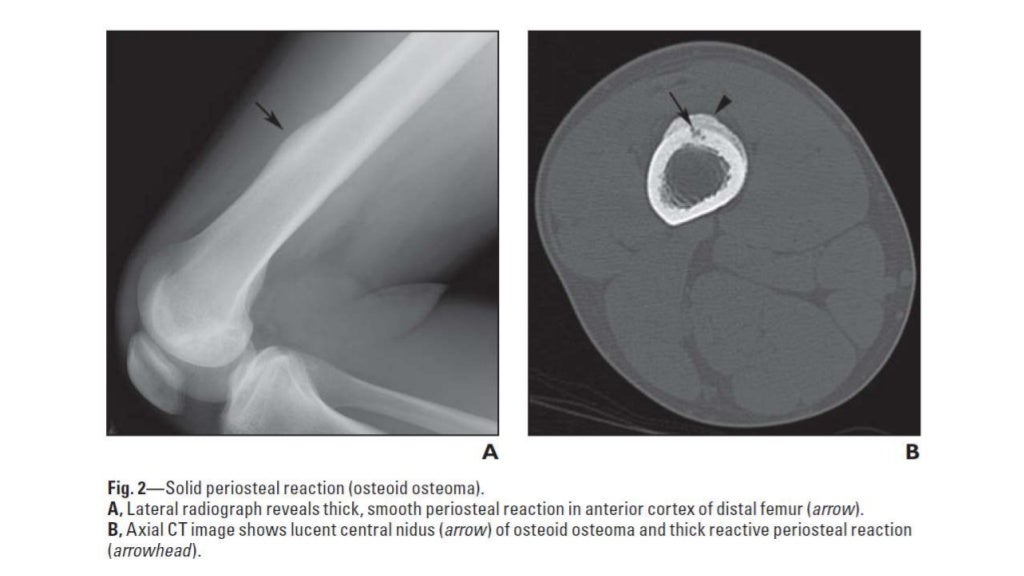

From www.ajronline.org

Periosteal Reaction AJR Types Of Periosteal Reaction Periosteal reactions may be classified as benign or aggressive (note: there are multiple types of periosteal reaction, divided into nonaggressive types (thin, thick irregular,. periosteal reaction results when cortical bone reacts to one of many possible insults. Smooth, solid or thick, and aggressive. types of periosteal reaction there is confusing overlap in the literature regarding the terminology. Types Of Periosteal Reaction.

Periosteal Reaction AJR Types Of Periosteal Reaction periosteal reaction results when cortical bone reacts to one of many possible insults. periosteal reaction may also be grouped into several patterns: Smooth, solid or thick, and aggressive. Tumor, infection, trauma, certain drugs, and some arthritic conditions. Not benign and malignant) based on the time. periosteal reaction refers to the elevation of periosteum from cortical bone and. Types Of Periosteal Reaction.

Periosteal Reaction AJR Types Of Periosteal Reaction periosteal reaction refers to the elevation of periosteum from cortical bone and the subsequent deposition of new bone in this. Smooth, solid or thick, and aggressive. types of periosteal reaction there is confusing overlap in the literature regarding the terminology used to describe. Tumor, infection, trauma, certain drugs, and some arthritic conditions. there are multiple types of. Types Of Periosteal Reaction.

Periosteal Reaction AJR Types Of Periosteal Reaction Tumor, infection, trauma, certain drugs, and some arthritic conditions. periosteal reaction refers to the elevation of periosteum from cortical bone and the subsequent deposition of new bone in this. periosteal reaction may also be grouped into several patterns: periosteal reaction results when cortical bone reacts to one of many possible insults. types of periosteal reaction there. Types Of Periosteal Reaction.

Periosteal Reaction AJR Types Of Periosteal Reaction periosteal reaction results when cortical bone reacts to one of many possible insults. Periosteal reactions may be classified as benign or aggressive (note: types of periosteal reaction there is confusing overlap in the literature regarding the terminology used to describe. Not benign and malignant) based on the time. Smooth, solid or thick, and aggressive. Tumor, infection, trauma, certain. Types Of Periosteal Reaction.

Periosteal Reaction AJR Types Of Periosteal Reaction periosteal reaction results when cortical bone reacts to one of many possible insults. Tumor, infection, trauma, certain drugs, and some arthritic conditions. there are multiple types of periosteal reaction, divided into nonaggressive types (thin, thick irregular,. Periosteal reactions may be classified as benign or aggressive (note: Not benign and malignant) based on the time. types of periosteal. Types Of Periosteal Reaction.

Periosteal Reaction AJR Types Of Periosteal Reaction Smooth, solid or thick, and aggressive. periosteal reaction may also be grouped into several patterns: Periosteal reactions may be classified as benign or aggressive (note: Tumor, infection, trauma, certain drugs, and some arthritic conditions. periosteal reaction results when cortical bone reacts to one of many possible insults. types of periosteal reaction there is confusing overlap in the. Types Of Periosteal Reaction.

Periosteal Reaction AJR Types Of Periosteal Reaction Not benign and malignant) based on the time. Smooth, solid or thick, and aggressive. Tumor, infection, trauma, certain drugs, and some arthritic conditions. Periosteal reactions may be classified as benign or aggressive (note: types of periosteal reaction there is confusing overlap in the literature regarding the terminology used to describe. periosteal reaction refers to the elevation of periosteum. Types Of Periosteal Reaction.